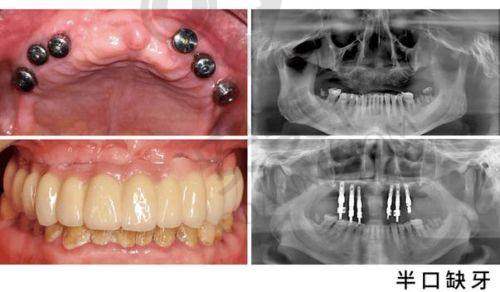

在娄底,牙齿缺失的患者们常常在寻找一家靠谱且性价比高的口腔医院来解决半口牙齿缺失的问题。娄底爱牙邦口腔的赵德强医生,在半口种植牙领域有着丰富的经验和出色的技术,其推出的半口种植牙项目30000元起,吸引了众多患者的关注。半口牙齿缺失不仅影响美观,更会对饮食和身体健康造成诸多不良影响,而种植牙作为目前较为理想的修复方式,娄底爱牙邦口腔赵德强医生的半口种植牙项目究竟有何独特之处,价格背后又隐藏着怎样的服务和技术呢?接下来,让我们一起深入了解。